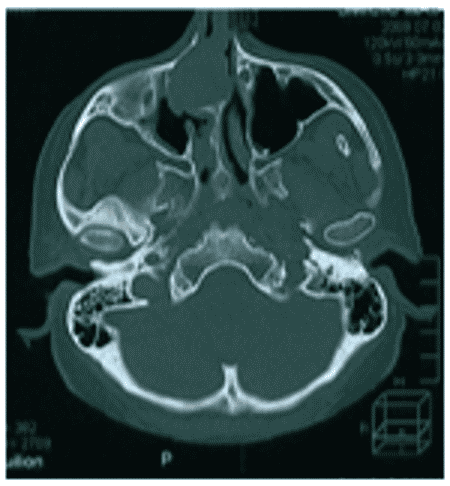

Остеобластома на КТ обычно представлена сочетанием плотной кости и участков затемнения (рисунок 4).

Рис. 4. КТ черепа, аксиальная плоскость. Гигантская остеобластома, распространяющаяся в правую орбиту, полость носа и переднюю черепную ямку

Данные КТ позволяют определить признаки локально агрессивного роста остебластомы, место ее исходного роста, наличие/отсутствие распространения опухоли за пределы околоносовых пазух.